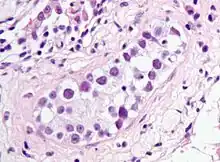

| Intratubular germ cell neoplasia. H&E stain. | |

GCNIS is not palpable, and not visible on macroscopic examination of testicular tissue. Microscopic examination of affected testicular tissue most commonly shows germ cells with enlarged hyperchromatic nuclei with prominent nucleoli and clear cytoplasm. These cells are typically arranged along the basement membrane of the tubule, and mitotic figures are frequently seen. The sertoli cells are pushed toward the lumen by the neoplastic germ cells, and spermatogenesis is almost always absent in the affected tubules. Pagetoid spread of GCNIS into the rete testis is common. Immunostaining with placental alkaline phosphatase (PLAP) highlights GCNIS cell membranes in 95 percent of cases. OCT3/4 is a sensitive and specific nuclear stain of GCNIS.[3]

ITGCN. H&E stain.

ITGCN. H&E stain.